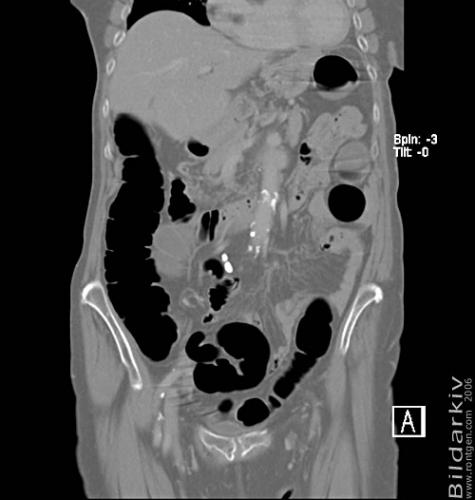

CT colon 22

Datortomografi av tjocktarmen (colon) med infunderad luft i tarmen samt med kontrast i blodbanan. Koronar bildserie.

CT multislice 16